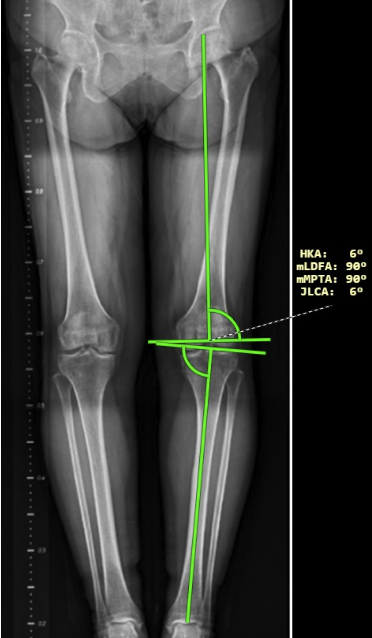

- Úhly dolní končetiny jsou v této verzi DICOM prohlížeče upraveny a nyní zobrazují také laterality úhlů. Lateralitu úhlů je možné určit pomocí pravého postranního panelu v „Pracovní sadě nástrojů měření“, rozbalovacího menu „Lateralita“ v záložce „Úhly dolní končetiny“. Po naměření úhlů dolní končetiny jsou zobrazeny tyto úhly:

- HKA – hip-knee-ankle angle

- mLDFA – mechanical lateral distal femoral angle

- mPTA – medial proximal tibial angle

- JLCA – joint line convergence angle